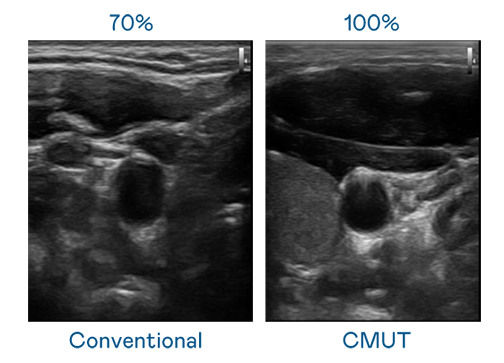

CMUT 技术是一种用电容式微机电元件来产生超音波讯号的技术。与传统 PZT 压电式技术相比,CMUT 频宽增加 30%,更宽频的超音波讯号让影像解析度大幅提升,是实现高影像品质医疗超音波扫描、促进精准医疗发展的关键技术。

大频宽带来超清晰影像

超音波影像的解析度高低,首先取决于探头能发出的讯号频宽。mg冰球突破 CMUT 可提供高清晰的超音波讯号,提供高频宽、高灵敏度、影像纹理细节更高的超音波影像,协助医护人员缩短影像判读时间及利用精准的医疗影像进行诊断。